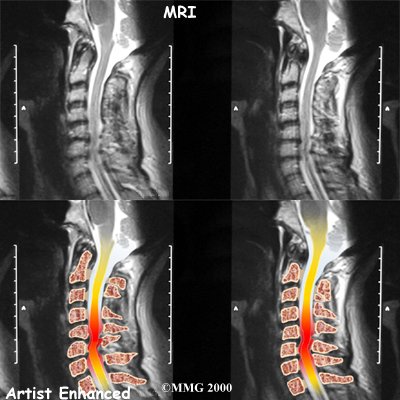

Stenosis means closed in. Spinal stenosis refers to a condition in which the spinal cord is closed in, or compressed, inside the tube of the spinal canal. Spinal stenosis may be caused by degenerative changes, such as bone spurs pushing against the spinal cord within the spinal canal.

Spinal Stenosis

However, stenosis can also develop when a person of any age has a disc herniation that pushes against the spinal canal. When the spinal cord is squeezed in the neck, doctors call the condition cervical myelopathy. This is an alarming condition that demands medical attention. Cervical myelopathy can cause problems with the bowels and bladder, change the way you walk, and affect your ability to use your fingers and hand.

Cervical Myelopathy